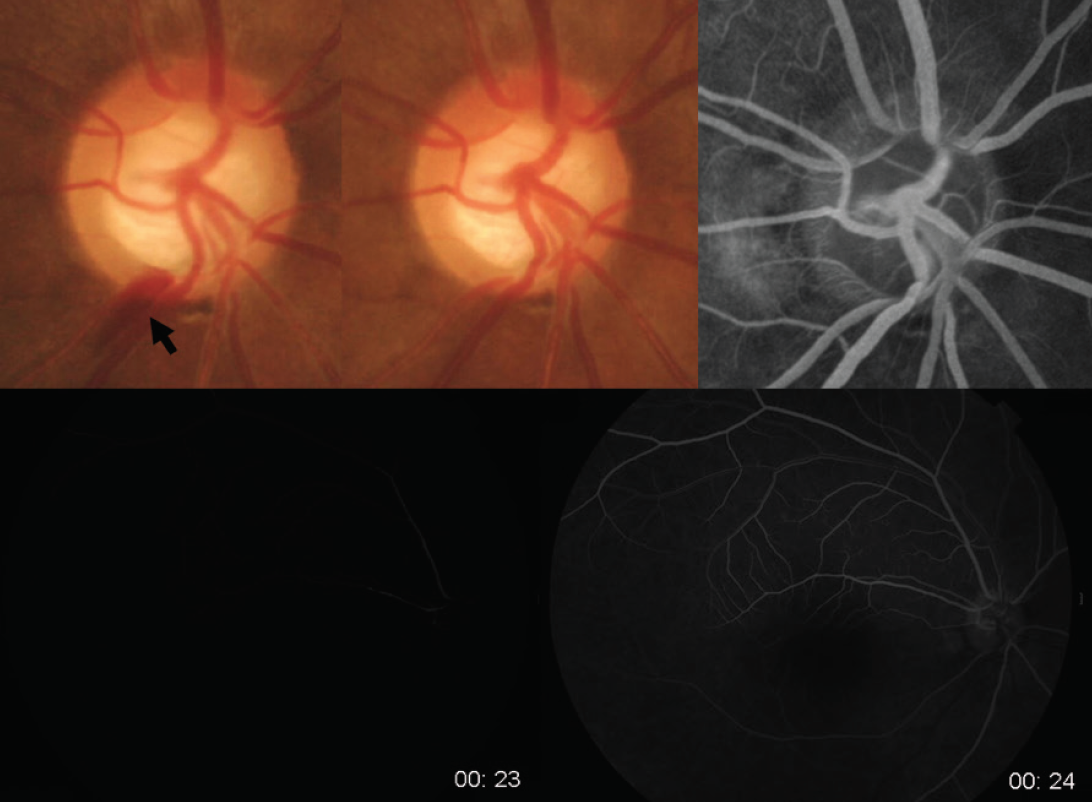

ODH suggests vascular damage and an increased likelihood that a significant vascular component is contributing to the disease when ODH occurs. Park et al23 studied 35 eyes with ODH to analyze the relationship among ODH, vascular abnormalities, and changes in the optic disc and RNFL. They found that approximately half of the eyes with ODH had accompanying localized RNFL defects. Of these eyes, 60% had vascular changes on fluorescein angiography at the site of the ODH (Figure 1). However, almost half of the eyes with ODH did not have an associated RNFL defect, and those eyes did not show vessel filling defects or delayed filling (Figure 2).

Figure 1. A 47-year-old woman with normal-tension glaucoma. ODH (black arrow) was present at the border of a localized retinal nerve fiber layer defect in her right eye (A). Fluorescein angiography was performed 3 months after disappearance of the ODH in the disc photograph (B). A vessel filling defect (white arrow) was found at the midarteriovenous phase (C), early late phase (D), and late phase of fluorescein angiography (E). The vessel filling defect was proximal to the location of the ODH. This vein is reflected at the cup margin, the proximal location of the ODH.

Figure 2. A 54-year-old woman with normal-tension glaucoma. ODH not related to a localized retinal nerve fiber layer defect shows no specific findings suggesting hemodynamic changes, such as vessel filling defect or delayed filling, disc leak, or disc filling defects.

(Courtesy of Park et al23)